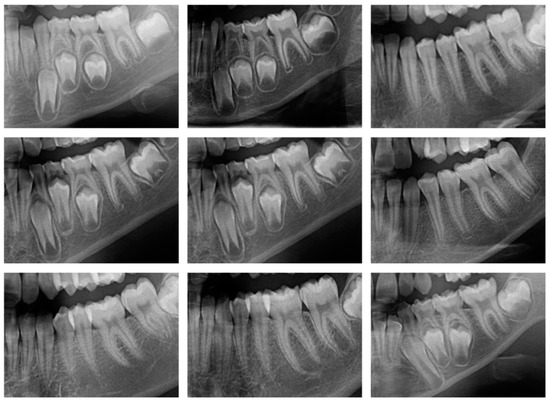

3.1. Dataset Description

3.2. Preprocessing